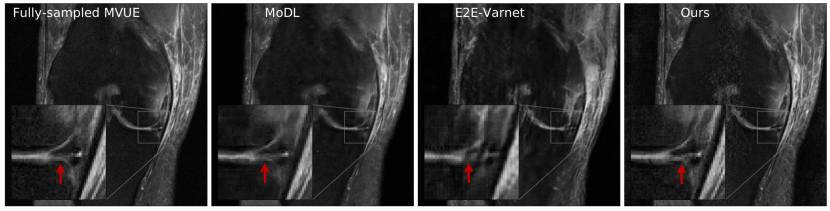

Refer to caption

Figure 4: Our method successfully recovers fine details and can provide an estimate of the reconstruction error. The left column shows a knee from the fastMRI dataset, along with an annotated meniscus tear (indicated by red arrow in zoomed inset). Given measurements at an acceleration factor of R=4𝑅4R=4, we obtain 484848 independent reconstructions via posterior sampling. The second column shows the pixel-wise average of reconstructions, the third column shows the pixel-wise standard deviation, and the fourth column shows the magnitude of the error between the ground truth and the mean reconstruction. Note that our generative prior has never seen such pathology, as it was trained on T2-weighted brain scans.

4.3 Uncertainty Estimation

Our method can also provide uncertainty estimates for each reconstructed pixel by running multiple reconstruction samplers. For a given observation y𝑦y, we can obtain independent samples x^1,,x^Kμ(|y)\widehat{x}_{1},\cdots,\widehat{x}_{K}\sim\mu(\cdot|y), for K𝐾K sufficiently large. Now, using the conditional mean estimate x¯=i=1Kx^i/K¯𝑥superscriptsubscript𝑖1𝐾subscript^𝑥𝑖𝐾\bar{x}=\sum_{i=1}^{K}\widehat{x}_{i}/K, we can compute the pixel-wise standard deviation i=1K|x^ix¯|2/Ksuperscriptsubscript𝑖1𝐾superscriptsubscript^𝑥𝑖¯𝑥2𝐾\sqrt{\sum_{i=1}^{K}|\widehat{x}_{i}-\bar{x}|^{2}/K}, and this gives an estimate of the error in each pixel. As shown in Fig 4, the pixel-wise standard deviation is a good estimate of the ground truth error |xx¯|superscript𝑥¯𝑥|x^{*}-\bar{x}|. Additionally, notice that the reconstructions are able to recover fine details such as the annotated meniscus tear222https://discuss.fastmri.org/t/219 in Fig 4 and predict low uncertainty for these features.

Figure 17 in Appendix D shows another example of an annotated meniscus tear. Figures 18 and 19 show comparisons with baselines on the same examples.